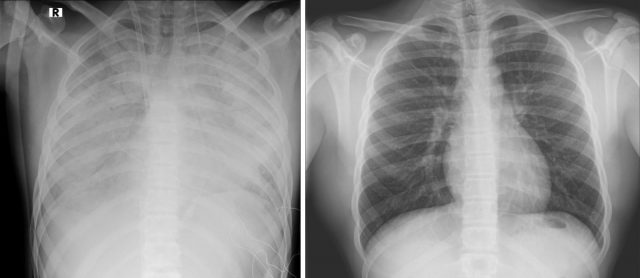

נער בן 16 מאושפז ביחידה לטיפול נמרץ לב במרכז שניידר לרפואת ילדים, במצב קשה לאחר שימוש בסיגריות אלקטרוניות. הנער הועבר למרכז שניידר מבית החולים קפלן, במצב של קריסת ריאות.

לדברי פרופ' עובדי דגן, מנהל היחידה לטיפול נמרץ לב: "הנער התקבל ליחידה לטיפול נמרץ לב במצב קשה מאד כשריאותיו אינן מתפקדות, והוא זקוק לתמיכה מלאה של מכשיר אקמו. אנו מטפלים בו ומקווים מאד לשיפור במצבו בימים הקרובים. הנזק שנגרם, ככל הנראה, מעישון של הסיגריות האלקטרוניות הוא נזק עצום. אנו קוראים לכל ההורים, מנעו את המקרה הבא".

ד"ר חבצלת ירדן בילבסקי, מומחית בפרמקולוגיה קלינית וטוקסיקולוגיה במרכז שניידר מוסיפה כי סיגריות אלקטרוניות עלולות לגרום נזק חמור אף יותר מסיגריות רגילות. בספרות הרפואית קיימים דיווחים רבים על מחלת ריאות משנית לשימוש יתר בסיגריות אלקטרוניות, עד כדי קריסת הריאות. בחלק מהמקרים חומרי המילוי נרקחים באופן עצמאי עם חומרים מסוכנים שונים, מה שמעלה את הסיכון לנזקים חמורים עוד יותר, ובמקרה הזה – לקריסת ריאות של נער בן 16. אני קוראת לבני הנוער ולהורים להיות עירניים וממליצה להתרחק מסיגריות אלקטרוניות ובוודאי לא להשתמש בחומרים מסוכנים שנרקחים עצמאית.